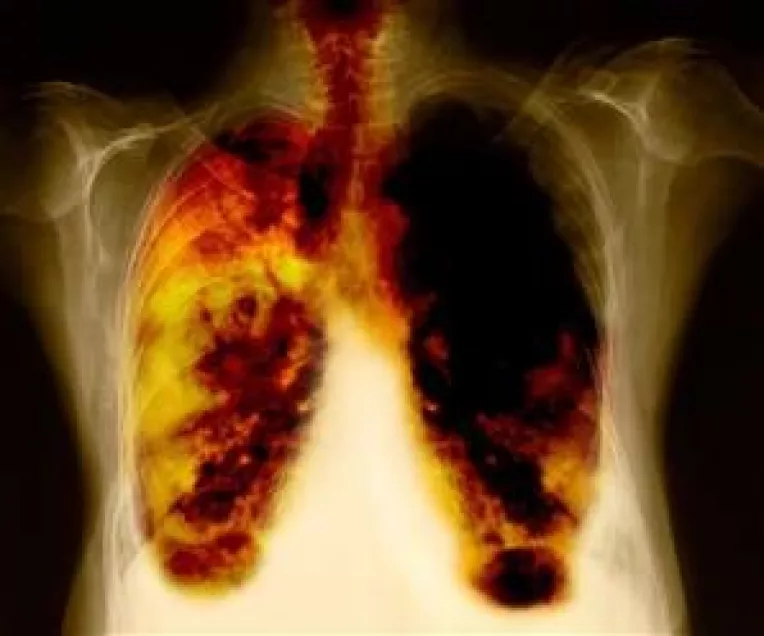

Federatia Asociatiilor Bolnavilor de Cancer (FABC) a lansat in luna noiembrie "Top 10 intrebari despre cancerul pulmonar" - un ghid destinat persoanelor diagnosticate cu cancer pulmonar, ce face parte din cadrul campaniei nationale de informare "Castiga timp! Cancerul pulmonar iti poate fura timpul".

Ghidul - care cuprinde si un dictionar explicativ al termenilor folositi in practica medicala - incearca sa raspunda celor mai frecvente 10 intrebari legate de cancerul pulmonar.

"Cancerul pulmonar este cel mai frecvent neoplasm in randul barbatilor si al patrulea ca frecventa la femei. In Romania, potrivit studiului Globocan din 20081, se inregistreaza o incidenta de 30 de cazuri la 100.000 de locuitori", subliniaza medicul Iustina Fusu, vicepresedintele Ligii Romane de Cancer.

"Impreuna cu partenerii nostri din aceasta campanie dorim sa atragem atentia asupra riscului acestei boli. Cancerul pulmonar este cel mai mare ucigas dintre toate. Numarul 1 in randul barbatilor, dar si boala oncologica cu cea mai mica durata medie de supravietuire... Este o afectiune care vine cu semne putine si ne lasa putin timp la dispozitie", atrage atentia Cezar Irimia, presedintele FABC.

Cauza principala a cancerului pulmonar este reprezentata, la peste 90% din pacienti de fumat. Statisticile arata ca, in randul barbatilor fumatori, riscul de aparitie a cancerului pulmonar este de 17%, in timp ce in randul femeilor fumatoare este de 12%. Persoanele care fumeaza mai mult de un pachet de tigari pe zi au un risc de a dezvolta cancer pulmonar de pana la 25 de ori mai mare decat un nefumator.

Diagnosticarea cancerului pulmonar este dificila, deoarece simptomele lui pot fi confundate cu cele ale unei raceli persistente sau cu tusea cauzata de fumat. In majoritatea cazurilor, afectiunea este diagnosticata cand deja se inregistreazs metastaze.